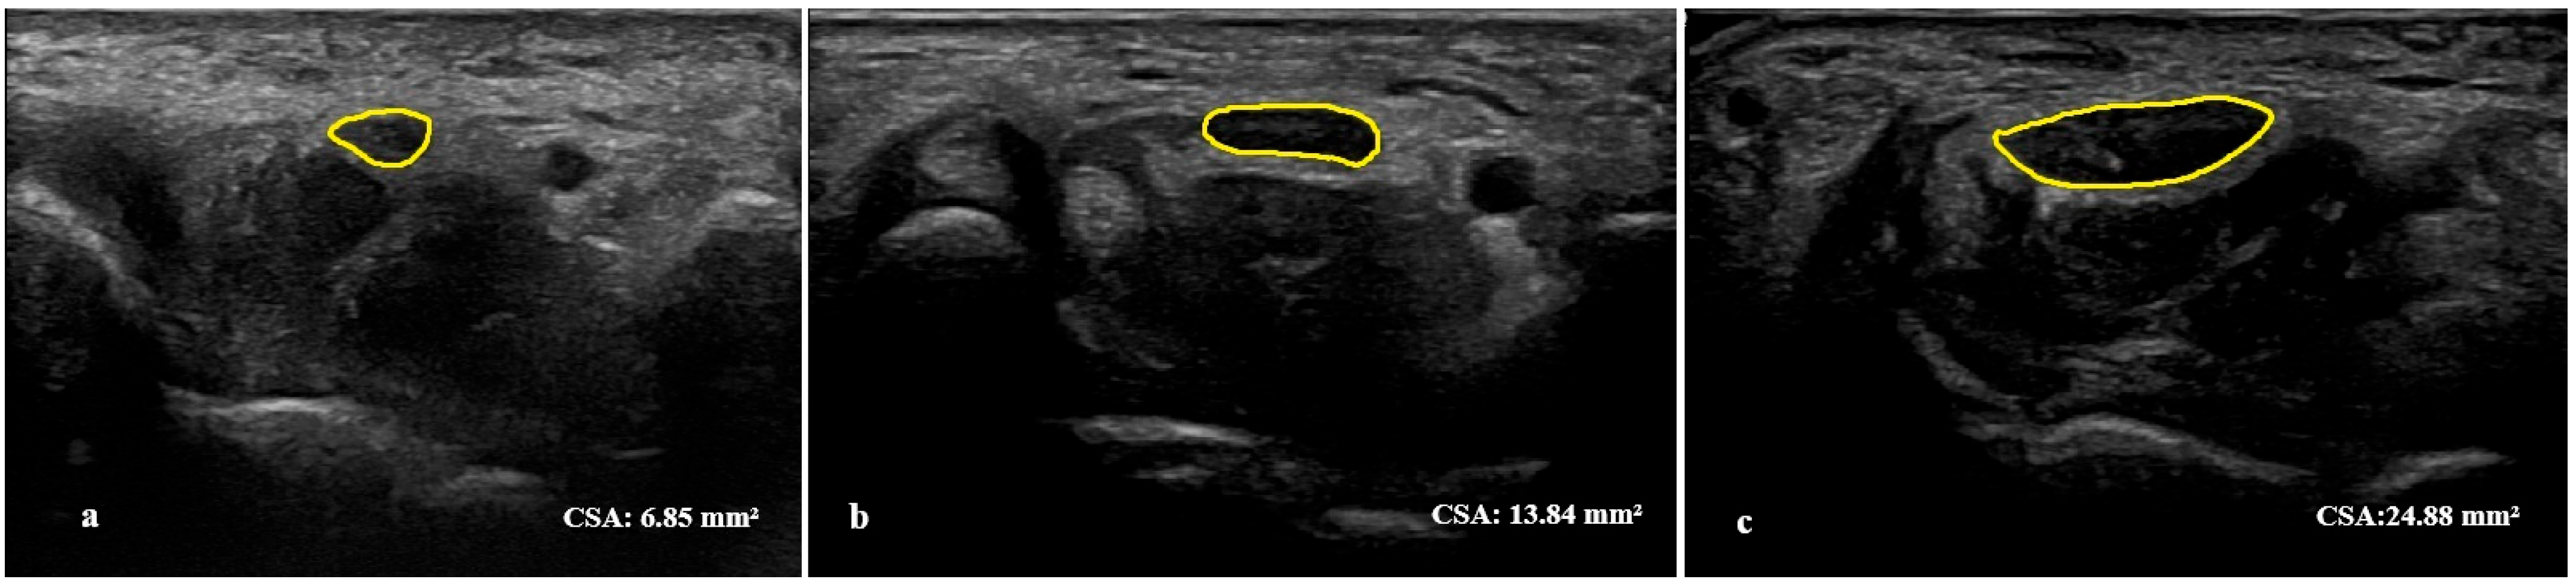

2.3. Ultrasonographic Assessment

| Median nerve CSA, mm2—right | 13.42 ± 4.26 (range: 6.73–26.2) |

| Median nerve CSA, mm2—left | 13.42 ± 3.84 (range: 7.88–24.4) |

| Median nerve CSA, mm2—most symptomatic side | 14.24 ± 4.34 (range: 7.43–26.2) |